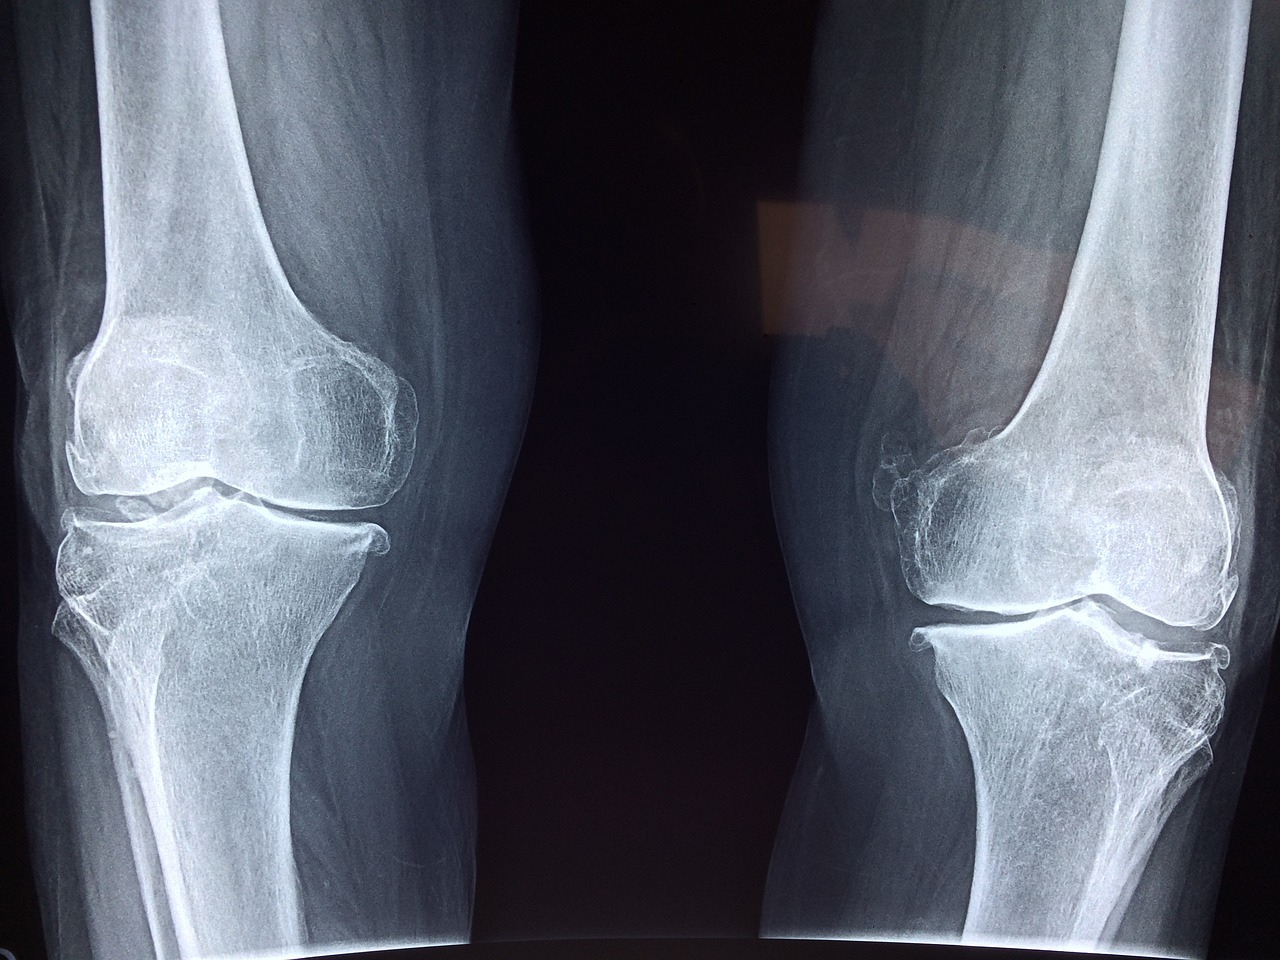

인공관절 수술은 손상된 관절을 인공 삽입물로 대체하는 치료법으로, 크게 전치환술(Total Knee Replacement, TKR)과 부분치환술(Partial Knee Replacement, PKR)로 나뉩니다.

- 퇴행성 관절염이 심하거나 연골 손상이 광범위한 경우 시행됩니다.

수술 방법 선택은 환자의 관절 상태, 나이, 활동 수준 등을 고려해 결정해야 합니다. 반드시 전문의와 상담 후 본인에게 맞는 수술법을 선택하는 것이 중요합니다.